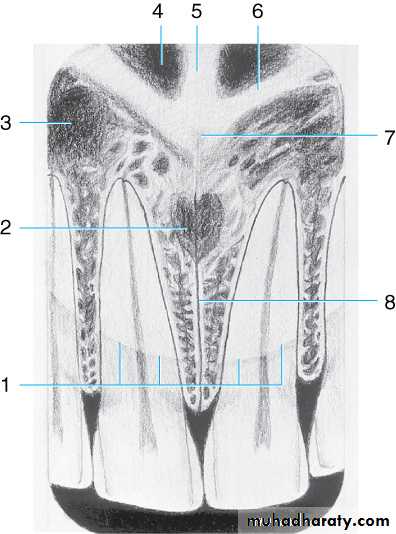

Drawing of maxillary midline area. Shown are the (1) outline of nose, (2) incisive foramen , (3) lateral fossa, (4) nasal fossa, (5) nasal septum, (6) border of nasal fossa, (7) anterior nasal spine, and (8) median palatine suture

Radiographic Anatomy Basics